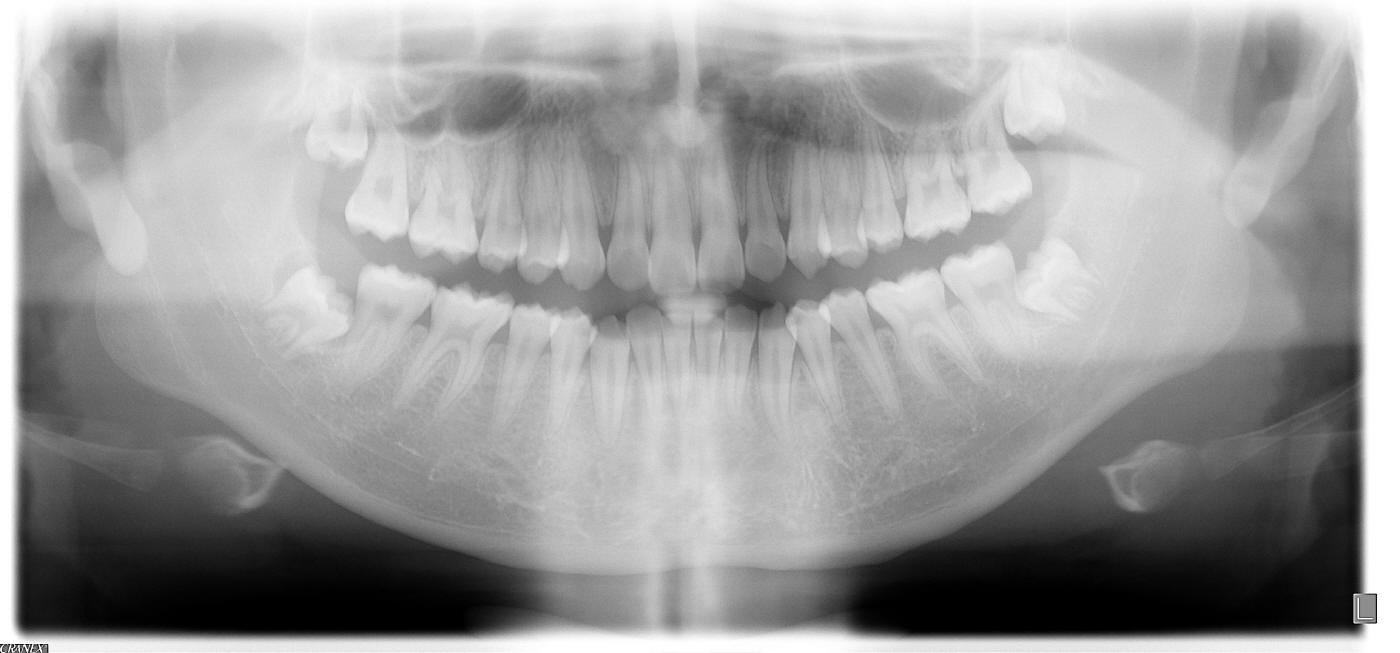

新病例:四颗智齿需要拔吗?

这次讨教大家:十六岁男孩,正畸医生建议拔除四颗智齿,然后做矫正,该拔吗?谢谢。放大全景片